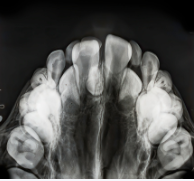

Le traitement orthodontique peut être effectué sur les dents de lait, ou en denture mixte si les dents de lait cohabitent avec des dents définitives.

Quels traitements sont-ils adaptés aux problèmes d'encombrement et de diastème ?